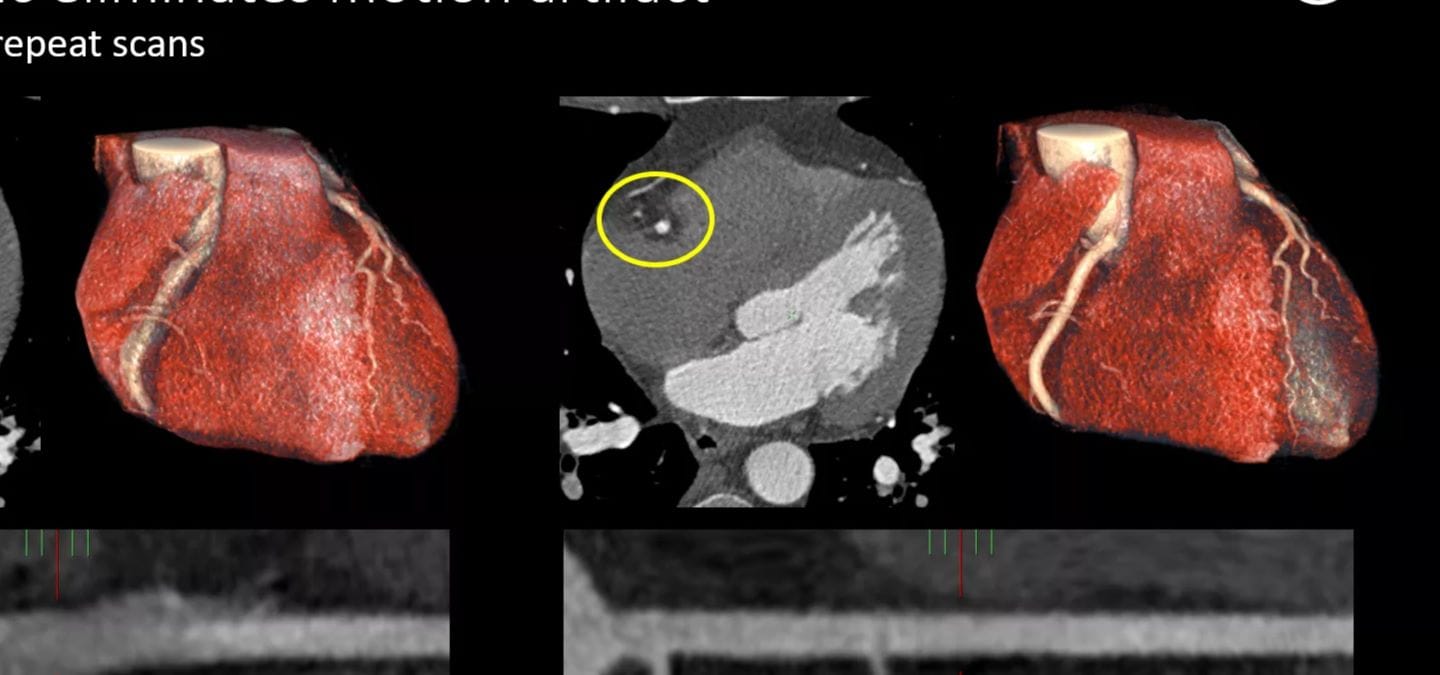

Op ESC 2024 presenteert Philips nieuwe echocardiografie toepassingen waarin gebruik wordt gemaakt van nog niet eerder beschikbare AI-toepassingen die helpen echocardiografiemetingen te versnellen en te automatiseren. Het nieuwe geavanceerde platform beschikt over innovatieve AI-tools die zijn ontworpen om de diagnose van structural heart diseases (SHD) te ondersteunen, waaronder een nieuwe geautomatiseerde 3D-tool voor tricuspidalisklepkwantificering [1] en nieuwe 3D-kleurstroomkwantificering om te helpen bij het diagnosticeren van mitralisinsufficiëntie.

Op de ESC 2024 wordt ook het nieuwste AI-gestuurde cardiovasculaire echografieplatform van Philips geïntroduceerd. Dit platform is het eerste in de sector met toepassingen die zijn ontworpen om met behulp van bewezen technologie de analyse van echocardiografische resultaten te versnellen. Dit platform is nu geïntegreerd met Philips Ultrasound Workspace en maakt hetzelfde mogelijk. Het ondersteunt consistente diagnostische mogelijkheden waardoor geavanceerde analyses van leveranciersonafhankelijke gegevens mogelijk zijn om de besluitvorming in het hele cardiologische zorgpad te verbeteren.